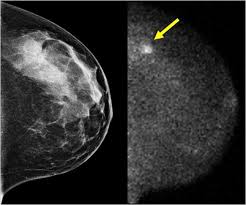

What does breast cancer look like? Breast cancer and some noncancerous (benign) breast conditions can appear white on a mammogram. Cancers may be seen as masses (like a ball, but usually with an irregular shape), areas of asymmetry that resemble normal tissue, calcifications (white specks), and/or areas of architectural distortion (imagine the puckering caused by pulling a thread in a piece of fabric). Abnormalities such as cancerous tumors usually appear brighter because they are denser. What does breast cancer look like on a mammogram?

This is considered an abnormal mammogram, but not necessarily one that's indicative of cancer. A fibroadenoma can look like a small marble, and you can move it under your skin. Cancers may be seen as masses (like a ball, but usually with an irregular shape), areas of asymmetry that resemble normal tissue, calcifications (white specks), and/or areas of architectural distortion (imagine the puckering caused by pulling a thread in a piece of fabric). However, cancer can also be seen as white, making it a bit obscure in women with extremely dense breasts. Calcifications are tiny flecks of calcium — like grains of salt — in the soft tissue of the breast that can sometimes indicate the presence of an early breast cancer. The mammogram and all other tests came back normal. There are few risks associated with mammography. Invasive breast cancer can appear as a white patch or mass on a mammogram.

What does cancer look like on a mammogram? A mammogram can show breast changes such as calcifications, masses, or other symptoms that might be cancer. Abnormalities such as cancerous tumors usually appear brighter because they are denser. Cancers may be seen as masses (like a ball, but usually with an irregular shape), areas of asymmetry that resemble normal tissue, calcifications (white specks), and/or areas of architectural distortion (imagine the puckering caused by pulling a thread in a piece of fabric). This is considered an abnormal mammogram, but not necessarily one that's indicative of cancer.

Cancers may be seen as masses (like a ball, but usually with an irregular shape), areas of asymmetry that resemble normal tissue, calcifications (white specks), and/or areas of architectural distortion (imagine the puckering caused by pulling a thread in a piece of fabric). Mammograms may show suspicious areas of the breast, white spots, and microcalcifications. Calcifications are tiny flecks of calcium — like grains of salt — in the soft tissue of the breast that can sometimes indicate the presence of an early breast cancer. Doctors use a mammogram to look for early signs of breast cancer. Abnormalities such as cancerous tumors usually appear brighter because they are denser. If you get an abnormal result for mammography and you have had uterine cncer and just checked your cancer antigen its 6.3. What does a suspicious area look like on a mammogram? They're often easy to move around (mobile) and may be tender. Regular mammograms are the best tests doctors have to find breast cancer early, sometimes up to three years before it can be felt. Invasive breast cancer can appear as a white patch or mass on a mammogram. A lump or tumor will show up as a focused white area on a mammogram. What does breast cancer look like on a mammogram? There are few risks associated with mammography.